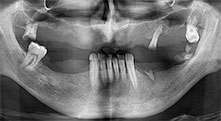

Bratu: Wir nutzen die Instrumente routinemäßig für die Entnahme von Knochenblöcken und das Spalten von Kieferkämmen. Weiterhin osteotomieren wir mit den Piezomed B6/B7 retinierte Zähne und entfernen nicht erhaltungsfähige Implantate. Alles Indikationen, bei denen es auf tiefe, saubere Schnitte ankommt.

Bratu: Wir bevorzugen Knochenentnahmen von der Linea obliqua externa des posterioren Unterkiefers, nicht aus der interforaminalen Region. Nach der Weichgewebsinzision verwenden wir die neuen Sägen, um den Umfang der Knochenentnahme zu definieren. Wir erledigen damit in fast 80 Prozent der Fälle auch die gesamte Präparation. Zusätzlich verwenden wir eventuell andere Piezo-Instrumente und zuletzt einen Meißel, um den Block zu mobilisieren. Das ist für uns eine sehr effektive Operationstechnik.

Bratu: Wir augmentieren im seitlichen Unterkiefer gern mit der Sandwich-Technik. Dabei wird ein Knochendeckel mit der Piezosäge präpariert und das krestale Fragment mit Mikroschrauben fixiert. Dazwischen platzieren wir eine Mischung aus autologem Knochen und xenogenem Knochenersatzmaterial. Das funktioniert sehr zuverlässig. Bei Kieferkammspaltungen im Unterkiefer sollten Sie nie auf ausreichend dimensionierte vertikale Schnitte verzichten. Sonst kann der Knochen leicht frakturieren.

Bratu: Ich halte Piezo für einen großen Sprung nach vorn für die Oralchirurgie. Die Technik macht Knochenpräparationen sicherer und leichter. Man verliert wenig Knochen, zum Beispiel bei Extraktionen. In der ästhetischen Zone ist dies sehr wichtig, vor allem wenn eine Sofortimplantation geplant ist. Auch für Weichgewebe ist Piezochirurgie ein Sicherheitsgewinn: Membranverletzungen in der Kieferhöhle sind im Prinzip Geschichte, ebenso Nervverletzungen bei Knochenblockentnahmen. Es gibt auch Daten, die geringere postoperative Schwellung und Beschwerden zeigen. Übrigens lassen sich mit Piezochirurgie auch sehr gut Kieferhöhlensepten präparieren. Nicht zuletzt profitieren unsere Patienten von der schonenden Arbeitsweise dieser Technik.